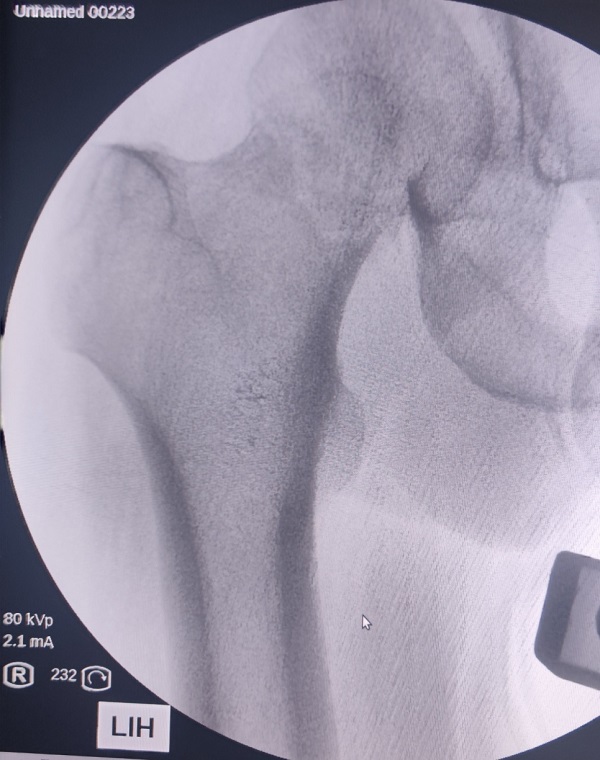

49岁的段先生在工地干活时不幸摔伤,被工友紧急送来咸阳骨科医院创伤骨科就诊。急诊拍片显示左侧股骨颈头下型、GardenⅣ型骨折。造成该类型骨折的暴力大,骨折移位严重,骨折周围血液循环受损严重,骨折不稳定,治疗效果差。伤后影像学检查结果如下:

术前X线片: